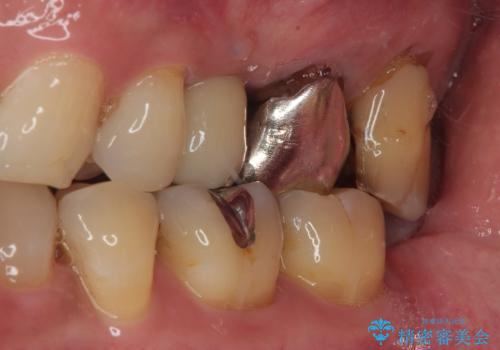

拡大鏡視野下で、セラミックの被せもの、虫歯の除去を行い、オールセラミッククラウンに適した形に整えました。

歯と歯茎の間に圧排糸と言われる糸を入れてシリコーン印象材にて型どりをしました。

今後もメンテナンスで通っていただきながら、経過観察していく予定です。